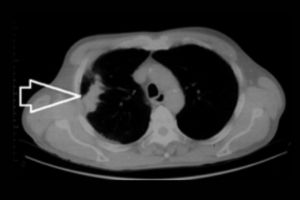

NCCT Temporal Axial and Coronal

Medifyhome offers NCCT Temporal Axial and Coronal scans, a non-contrast computed tomography (NCCT) imaging service for the temporal bone of the skull. This type of scan gives you detailed axial and coronal views of the temporal bones, which protect the inner ear structures and surrounding tissues. Recommended for patients with hearing loss, dizziness, infections, or trauma-related injuries, the NCCT Temporal scan helps to detect and diagnose fractures, infections, or abnormalities that affect balance, hearing, and facial functions. Medifyhome’s service uses advanced equipment and experienced professionals to ensure accurate imaging, so you can trust us for precise diagnostic care. With Medifyhome’s NCCT Temporal Axial and Coronal scans, you get high-quality imaging to support diagnosis and treatment plans.

What is an NCCT Temporal Axial and Coronal Scan?

An NCCT Temporal Axial and Coronal Scan is an imaging diagnostic test, where an X-ray or computed tomography (CT) scan will give a non-contrast two-dimensional view of the image of the temporal bone located inside the skull. A high-resolution scan in axial or coronal view allows health workers to assess inner ear structures efficiently. The main clinical condition diagnosed by this scanning tool is fracture, infections, and other abnormalities involving an impairment in hearing or maintaining balance. This makes the scan a very useful tool in the diagnosis and treatment of patients with otologic or neurologic disorders.